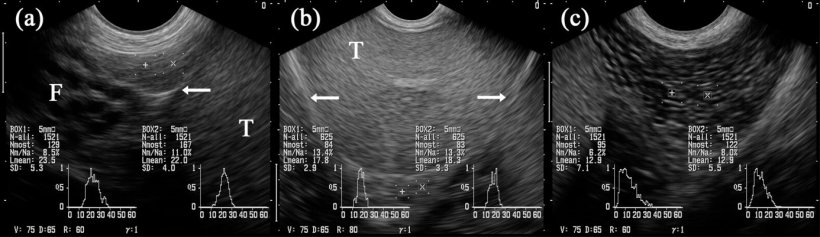

En général, le tissu de l'épididyme est également d'une échostructure homogène et régulière, en étant plus fine dans la tête et le corps et légèrement marbré dans la queue (figure 5A-C). Cependant, l'échogénicité, déterminée par l '« analyse des niveaux de gris », et donnée comme la valeur de gris moyenne, diffère légèrement entre les trois segments, avec des changements dans les images obtenues en comparant avant et après la collecte de la semence (Kauffold et al., 2011) du verrat.

Figure 5: images échographiques des segments épididymaires: caput (= tête, a), corpus (b) et cauda (= queue; c). Les cases marquées « + » et « x » sont projetées sur les segments respectifs de l'épididyme. Testicule (T). Adjacente à la tête il y a plusieurs structures tubulaires identifiées comme étant des parties du funiculus spermaticus (F). Les flèches indiquent la couverture séreuse du testicule (c'est à dire la bursa) testicularis. (Kauffold et al., 2011)